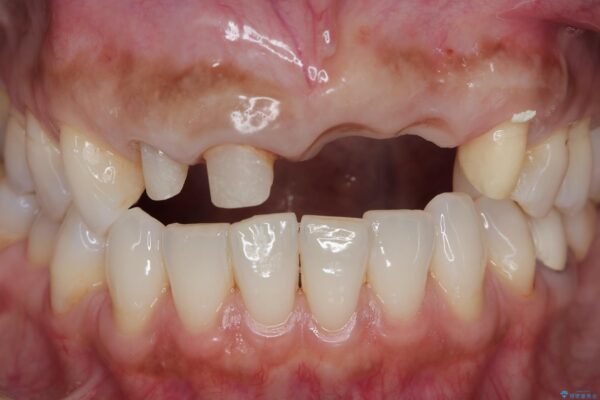

治療前

歯槽堤保存術を併用したブリッジ治療 治療前画像 歯槽堤保存術を併用したブリッジ治療 治療前画像 歯槽堤保存術を併用したブリッジ治療 治療前画像 歯槽堤保存術を併用したブリッジ治療 治療前画像 歯槽堤保存術を併用したブリッジ治療 治療前画像 歯槽堤保存術を併用したブリッジ治療 治療前画像 歯槽堤保存術を併用したブリッジ治療 治療前画像 歯槽堤保存術を併用したブリッジ治療 治療前画像 歯槽堤保存術を併用したブリッジ治療 治療前画像 歯槽堤保存術を併用したブリッジ治療 治療前画像

一見して問題ないように見える左側の2前歯は、セラミックを除去してみると亀裂や虫歯の再発が見られました。

抜歯時に可及的に歯肉のボリュームを保つよう骨充填材とコラーゲン製剤による填塞を行い審美的かつ機能的なブリッジとなるよう治療を進めます。